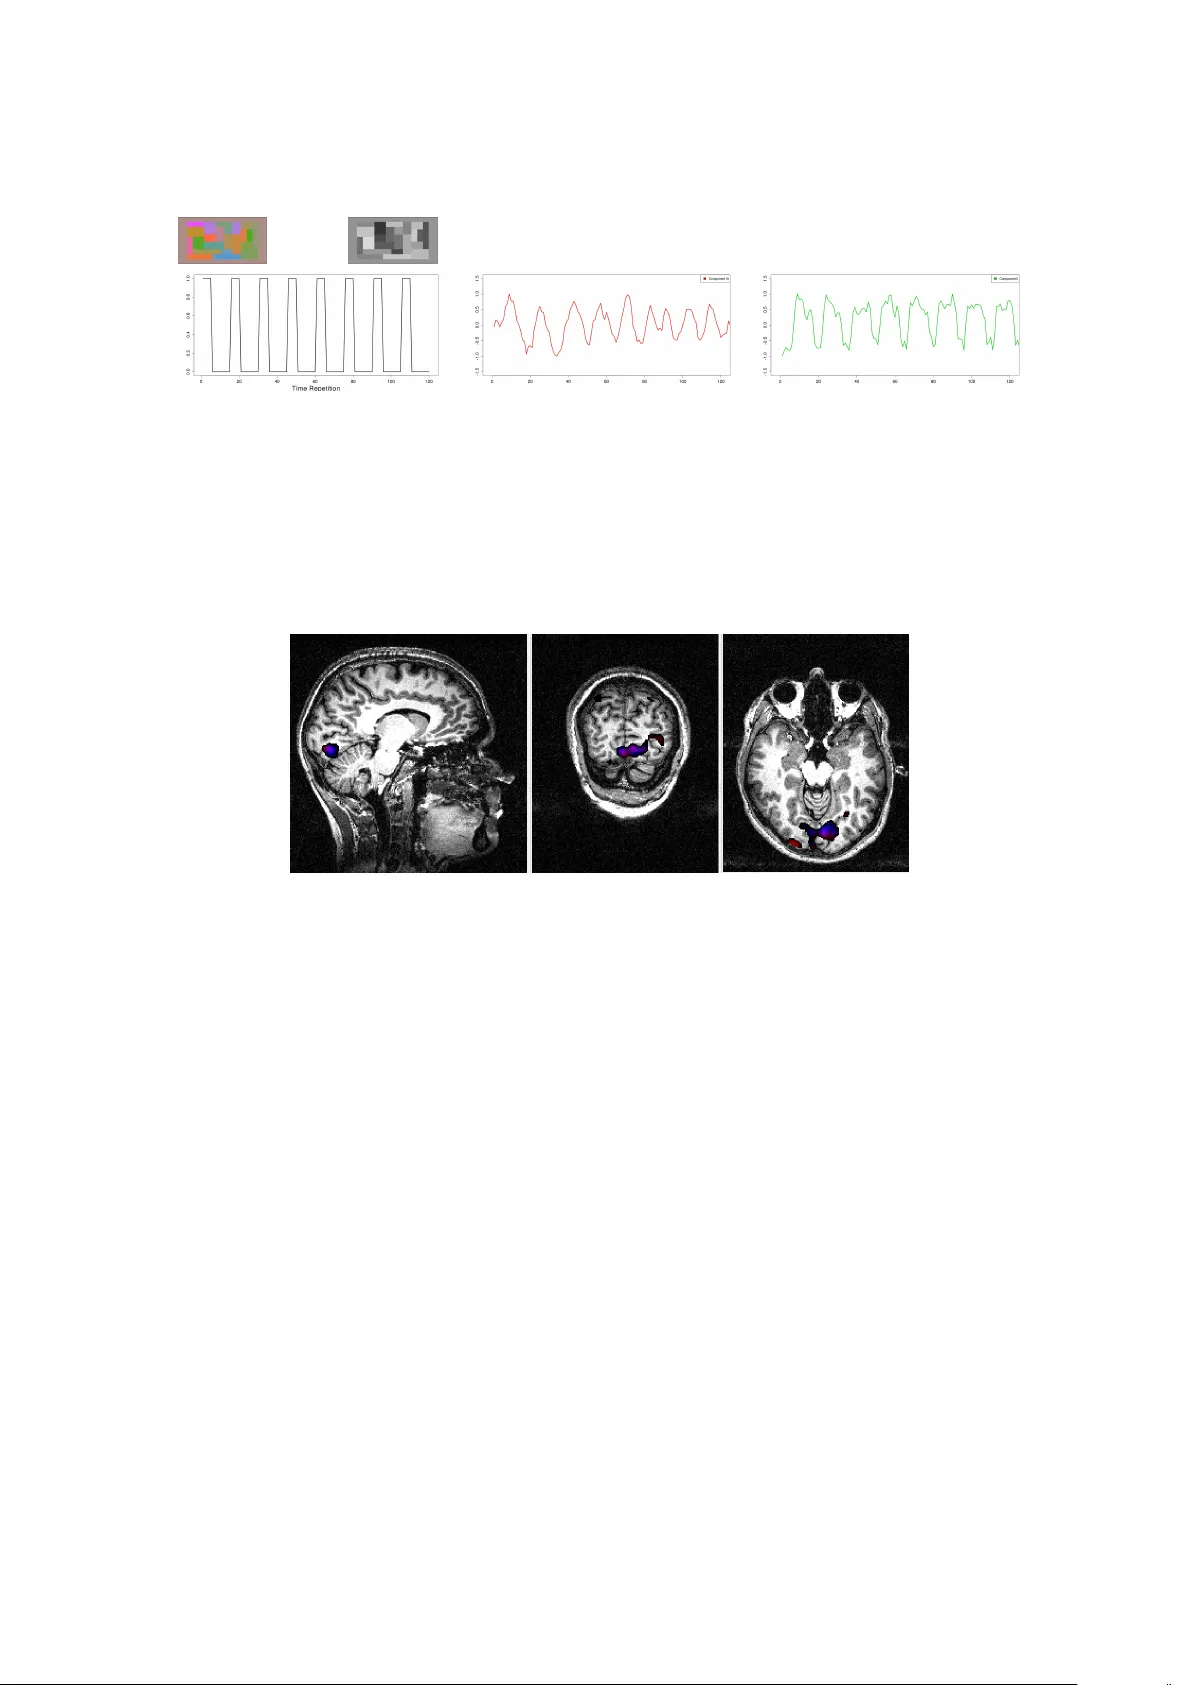

T emp oral and Spatial Indep enden t Comp onen t Analysis for fMRI data sets em b edded in a R pac k age C ´ ecile Bordier GIN Mic hel Do jat GIN Pierre Lafa y e de Mic heaux Univ ersit´ e de Mon tr´ eal Abstract F or statistical analysis of functional Magnetic Resonance Imaging (fMRI) data sets, w e propose a data-drive n approach based on Independent Component Analysis (ICA) im- plemen ted in a new ver sion of the AnalyzeFMRI R pack age. F or fMRI data sets, spatial dimension b eing muc h greater than temporal dimension, spatial ICA is the tractable ap- proac h generally prop osed. How ever, for some neurosc ien tific applications, temp oral inde- p endence of source signals can b e assumed and temp oral ICA b ecomes then an attracting exploratory technique. In this work, we use a classical linear algebra result ensuring the tractabilit y of temporal ICA. W e rep ort several exp eriments on syn thetic data and real MRI data sets that demonstrate the p otential interest of our R pack age. Keywor ds : Multiv ariate analysis, T emp oral ICA, Spatial ICA, Magnetic Resonance Imaging, Neuroimaging. 1. In tro duction Magnetic Resonance Imaging (MRI) is no w a prominen t non-inv asive neuroimaging tec hnique largely used in clinical routine and adv anced brain research. Its success is largely due to a com bination of at least three factors: 1) sensitivity of MR signal to v arious physiological pa- rameters that c haracterize normal or pathological living tissues (such as diffusion properties of H 2 0 molecules, relaxation time of proton magnetization or blo o d oxygenation) leading to a v ast panoply of MRI mo dalities (resp ectiv ely restricted in our example to diffusion MR imag- ing, w eighted structural images and functional MRI); 2) constant hardware improv emen ts (e.g. mastering high field homogeneous magnets and high linear magnetic field gradients re- sp ectiv ely allo ws an increasing of spatial resolution or a reduction of acquisition time); and 3) sustained efforts in v arious lab oratories to dev elop robust softw are: for image pro cessing (to de-noise, segment, realign, fusion or visualize MR brain images), for computational anatomy leading to the exploration of brain structure mo difications during learning, brain dev elopmen t or pathology ev olution and for time course analysis of functional MRI data. Statisticians play a key role in this last factor since data pro duced are complex: noisy , highly v ariable b etw een sub jects, massive and, for functional data, highly correlated b oth spatially and temporally ( Lange ( 2003 )). F unctional MRI (fMRI) allows to detect the v ariations of cerebral blo o d ox ygen level induced b y the brain activit y of a sub ject, lying inside a MRI scanner, in resp onse to v arious sensory- 2 T emp oral and Spatial Indep endent Comp onent Analysis for fMRI data sets motor or cognitive tasks ( Chen and Ogaw a ( 1999 )). The fMRI signal is based on changes in magnetic susceptibilit y of the blo o d during brain activ ation. It is a non-in v asive and indi- rect detection of brain activity: the signal detected is filtered by the hemo dynamic resp onse function (HRF) and the neuro-v ascular coupling is only partially explained ( Logothetis and Pfeuffer ( 2004 )). The main goal of fMRI exp eriments is to explore, in a repro ducible w a y , the cortical netw orks implicated in pre-defined stim ulation tasks in a cohort of normal or pathological sub jects. The low signal to noise ratio obtained in functional images requires to rep eat the sequence of stimuli sev eral times ( Henson ( 2004 )) and to enroll a sufficient n umber of sub jects ( Thirion, Pinel, Meriaux, Ro che, Dehaene, and Pol ine ( 2007 )). In general, the data resulting from an fMRI exp erimen t consist in a set indexed with time (typically many h undred) of 3D dimensional functional images with a 3 × 3 × 3 mm 3 spatial resolution, and in a structural (or anatomical) image with a 1 × 1 × 1 mm 3 resolution used to accurately localize functional activ ations. Note that a 3D image is in fact an arra y of man y v oxels’s in tensities. V arious pre-pro cessing steps are required to correct functional i mages from possible head sub- ject mo vemen t, to realign functional and anatomical individual images and, for group studies, all individual data sets in a common referen tial. A spatial smo othing (e.g. using a gaussian k ernel) is generally applied to functional images to comp ensate for p otent ial mis-realignmen t and enhance the signal-to-noise ratio. Sev eral frameworks hav e b een prop osed to date for statistical analysis of these pre-pro cessed sets of functional data (see Lazard ( 2008 )’s b o ok for a recen t rev iew). The commonly used sta- tistical approach , massiv ely univ ariate, considers each vo xel indep endently from each other using regression techniques ( F riston, Holmes, P oline, F rith, and F rack o wiak ( 1995 )); Bull- more, Brammer, Williams, Rab e-Hesketh, Janot, David, Mellers, How ard, and Sham ( 1996 )). It is av ailable in freew are pac k ages such as FSL ( http://www.fmrib.ox.ac.uk/fsl/ ), SPM ( http://www.fil.ion.ucl. ac.uk/spm/ ), BrainVisa ( http://brainvisa.info/ ) or NIPY ( http://nipy.sourceforge .net/ ). The time series resp onse at each v oxel is mo deled as a stationary linear filter where the finite impulse resp onse corresp onds to a mo del of the HRF. This leads to the specification of a general linear model (noted GLM thereafter; not t o be con- founded with the Generalized Linear Mo del) where the design matrix contains, for eac h time p oin t, the o ccurrences of the successiv e stimuli (regressors) conv olv ed with the HRF mo del. Other regressors can b e seamlessly in tro duced to model possible confounds. Many refinemen ts to this approac h hav e b een prop osed ( Nic hols and Holmes ( 2002 ); F riston, Stephan, Lund, Morcom, and Kieb el ( 2005 ); Ro che, Meriaux, Keller, and Thirion ( 2007 )). Spatial smo oth- ness of the activ ated areas, normal distribution and indep endence of the error terms and a predefined form of the HRF used as a con volution kernel are the main a priori incorp orated in to the GLM. This mo del-driv en approach allows to test, using standard Studen t or Fisher tests, the activ ated regions against a desired h yp othesis by sp ecifying comp ositions of regres- sors. It is largely used essentially b ecause of its flexibility in mo del sp ecification allowing to test v arious h yp othesis represen ted in corresponding statistical parametric maps. Clearly , the v alidity of the interpretation of these maps dep ends on the accuracy of the sp ecified mo del. An alternative exploratory (data-driv en) approac h relies on multiv ariate analysis based on Indep enden t Component Analysis (ICA). ICA performs a blind separation of independent sources from a complex mixture of man y sources of signal and noise. In this approac h, relying on the int rinsic structure of the data, no assumptions ab out the form of the HRF or the p os- sible causes of resp onses are inserted. Only the num b er of sources or comp onents to search for could even tually b e sp ecified. T o identify a n umber of unknown sources of signal, ICA as- sumes that these sources are mu tually and statistically indep endent in space (sICA) or time C ´ ecile Bordier, Michel Do jat, Pierre Lafay e de Mic heaux 3 (tICA). This assumption is particularly relev ant to biological time-series ( F riston ( 1998 )). F or fMRI data set analyses, sICA is preferred b ecause temp oral p oint s (few hundr eds, corre- sp onding to each o ccurrence of a functional image acquisition) are small compared to spatial ones (more than 10 5 , corresp onding to the num b er of v oxels contained in a functional image) leading for tICA to a com putationnaly in tractable mixing matrix ( McKeo wn, Makeig, Bro wn, Jung, Jindermann, Bell, and Sejnowski ( 1998 )). Ho wev er, temp oral ICA could b e relev ant for some neuroscientific applications where temp oral independence of sources can b e assumed ( Calhoun, Adali, P earlson, and Pek ar ( 2001 )). In this context, these authors wrote “... Note that tICA is typic al ly much mor e c omputational ly demanding than sICA for functional MRI applic ations b e c ause of a higher sp atial than temp or al dimension and c an gr ow quickly b eyond pr actic al fe asibility. Thus a c ovarianc e matrix on the or der of N 2 (wher e N is the numb er of sp atial voxels of inter est) must b e c alculate d. A c ombination of incr e ase d har dwar e c ap acity as wel l as mor e advanc e d metho ds for c alculating and storing the c ovarianc e matrix may pr ovide a solution in the futur e ...” . In this pap er, we prop ose to use a classical linear algebra result to alleviate the aforementioned computational burden. The pap er is structured as follows. First, in Section 2 we briefly describ e the principle of temp oral and spati al ICA in the context of fMRI data set analysis and detail the mathe matical dev elopments we prop ose for ensuring temp oral ICA tractabilit y . In Section 3, w e describe the curren t v ersion of the AnalyzeFMRI R pack age (see Marc hini and Lafa ye de Micheaux ( 2010 )), whic h is the first R pack age designed for the pro cessing and analysis of large anatomical and functional MRI data sets. It was initiated b y J. Marc hini ( Marchini ( 2002 )), who passed the torch in 2007 to the third author of this pap er. This pack age includes, compared to its initial v ersion, our recen t extensions: i.e. NIFTI format managemen t, cross-platform visualization based on Tcl-Tk comp onents and temp oral (and spatial) ICA (TS-ICA). W e rep ort, in Section 4, results using synthetic data and real MRI data sets coming from h uman visual exp eriment s, obtained using TS-ICA. Finally , w e conclude ab out the interest of the AnalyzeFMRI pack age and our extensions for the exploration of MRI data and outline our plans for future extensions. 2. Spatial and T emp oral Indep enden t Comp onen t Analysis Indep enden t comp onent analysis (ICA) is a statistical tec hnique whose aim is to recov er hid- den underlying source signals from an observ ed mixture of these sources. In standard ICA, the mixture is supposed to b e linear and the only h yp othesis made to solve this problem (kno wn as the blind source separation problem) is that the sources are statistically m utually indep enden t and are not Gaussian. The generativ e linear instantaneous noise-free mixing ICA mo del is generally written under the form X = A S (1) where X = ( X 1 , . . . , X m ) T is the m × 1 contin uous-v alued random v ector of the observ able signals, A = ( a ij ) is th e unkno wn constan t (non random) and in vertible square mixing matrix of size m × m and S = ( S 1 , . . . , S m ) T is the m × 1 contin uous-v alued random vector of the m unkno wn source signals to b e recov ered. Note that if w e denote by B the inv erse of matrix 4 T emp oral and Spatial Indep endent Comp onent Analysis for fMRI data sets A , then we can write S = B X . The term “recov er” here means that we w ant to b e able, based on an observed sample x 1 , . . . , x n (p ossibly organised in a matrix X of size n × m ) of the random vector X , to estimate the densities f S j of the m sources S j , or at least to b e able to build an “observ ed” sample of size n of each one of these m sources, which are usually called the independent (extracted) componen ts. F or example, this sample could b e computed, if one has an estimate ˆ B of the separating matrix B , as s 1 , . . . , s n where s i = ˆ B x i , 1 ≤ i ≤ n . Note also that, using the indep endence prop erty of the sources, the density of the random v ector X can b e expressed as f X ( x ) = | A − 1 | f S ( s ) = | B | m Y j =1 f S j ( s j ) . It then follows that one can write the Log-likelihoo d of the observed sample as Log L ( B ) = Log n Y i =1 f X ( x i ) = n Log | B | + n X i =1 m X j =1 Log f S j ( b T j x i ) where b j denotes the j th column of B . This is easy to pro ve when one notices that S j = b T j X . No w, it remains to compute ˆ B = Argmax Log L ( B ) using some optimization algorithm. T o p erform this op eration, prior densities for the sources, or a simple parametrization of the sources can b e considered (see details in ( Hyv arinen, Karh unen, and Oja 2001 , p.205-6)). Alternativ es approac hes, not necessarily based on the likelihoo d function, are av ailable to estimate B (and th us S ). F or example, there is a relation b etw een indep endence and non gaussianit y ( Cardoso ( 2003 )). In our pack age, we used the F astICA algorithm which consists in finding the sources that are maximally non Gaussian, where non gaussianit y is measured using the kurtosis, see Hyv arinen et al. ( 2001 ). T o apply standard ICA techniques on fMRI data sets, the first step is to obtain a 2D data matrix X from the 4D data arra y resulting from an fMRI exp erimen t (the 4D arra y is the concatenation in time of seve ral 3D functional v olumes). This can b e p erformed in t w o (dual) w ays: (a) one may consider that the data consist in the realization of t l random v ariables, each one measured (sampled) on v l v oxels. This results in t l 3D spatial maps of activ ation. Eac h 3D map is then unrolled (in an arbitrary order) to get a matrix X of size v l × t l . The mixing matrix A is in this case of size t l × t l . (b) one may consider that the data consist in the realization of v l random v ariables, each one measured at t l time p oints. This results in v l time courses each one of length t l , collected into a matrix X of size t l × v l (here again, the order of the v l time courses in the resulting matrix is arbitrary). The mixing matrix A is in this case of size v l × v l . Using these data, the empirical counterpart of the noise-free mo del ( 1 ) can then b e written as X T = AS T (2) C ´ ecile Bordier, Michel Do jat, Pierre Lafay e de Mic heaux 5 where X =    x 1 . . . x n    and S =    s 1 . . . s n    . Case (a) corresp onds to spatial ICA (sICA) and the ro ws of matrix S T con tain spatially inde- p enden t source signals of length n = v l (unrolled source spatial maps). Case (b) corresp onds to temp oral ICA (tICA) and the ro ws of matrix S T con tain here temp orally indep endent source signals of length n = t l (source time courses). Note that the ro w-dimension of matrices X and S ab ov e corresponds to sample size, whic h is the classical statistical comm unity’s con ven tion (but not the neuroimaging comm unit y one where matrices should b e transp osed). A t this p oint, one ma y hav e noticed that, b ecause the mixing matrix A is square in standard ICA ( Hyv arinen et al. 2001 , p.267), in writing ( 2 ) w e hav e implicitly supp osed that the num b er of sources m is equal to t l in case (a) and v l in case (b). This is not necessarily the case. Data pre-pro cessing based on PCA is generally used to ov ercome this problem. Doing this, mo del ( 2 ) should b e re-written as Λ − 1 / 2 red E T red ˙ X T = AS T (3) where Λ red (resp. E red ) is the ( r e duc e d ) matrix whose diagonal elements (resp. columns) consist of the m largest (non null) eigen v alues (resp. eigenv ectors) of the empirical cov ariance (or ev entuall y correlation) matrix ˙ X T ˙ X /n (note that th e mixing matrix in to ˙ X T is then giv en b y A X = E red Λ 1 / 2 red A ). The size of the matrix E red is respectively t l × m in case (a) and v l × m in case (b ). Note also that t he Singular V alue Decomp osition (SVD) of matrix ˙ X can be used: ˙ X = U DV T and then replace, in equation ( 3 ), Λ red with D 2 red /n where D red is the diagonal matrix consisting of the m largest singular v alues of D , and E red with V red refering to the asso ciated singular vectors. Equation ( 3 ) then leads to the following decomp osition: ˙ X T = 1 √ n V red D red AS T = m X j =1 A X • j ⊗ S • j , (4) where S • j denotes the j th column of S . Note that the pair ( A X • j , S • j ) is sometimes (abu- siv ely) called the j th indep enden t (estimated) comp onen t, although this term should b e used solely for S • j , whereas A X • j refers to the weigh ting co efficients (degree of expression) of the j th spatial comp onen t ov er time (for sICA) or of the j th temp oral source o ver space, i.e. o ver the vo xels (for tICA). Figure ( 1 ) b elow is an illustration of equation ( 4 ) for sICA. 6 T emp oral and Spatial Indep endent Comp onent Analysis for fMRI data sets Figure 1: Illustration of the sICA decomp osition after a PCA pre-pro cessing step. No w, due to the large n umber of vo xels in fMRI exp eriments, it is not computationally tractable to fully diagonalize the correlation matrix in the temporal case (whic h is in this case of size v l × v l ). So tICA, as far as w e know, has never b een applied on the en tire brain v olume but only on a small p ortion of it ( Calhoun et al. ( 2001 ); Seifritz, Esp osito, Hennel, Mustovic, Neuhoff, Bilecen, T edeschi, Sc heffler, and Di Salle ( 2002 ); Hu, Y an, Liu, Zhou, F riston, T an, and W u ( 2005 )). Our extension to the R pac k age AnalyzeFMRI for TS-ICA uses a nice prop ert y of the SVD decomp osition that allo ws to obtain the non-zero eigenv alues (and their asso ciated eigenv ec- tors) of the correlation matrix in the temporal case. It then b ecomes feasible to p erform tICA for fMRI data on the whole brain volume. W e now briefly present this result. Theorem 1. The lar gest eigenvalues of the (huge) c ovarianc e matrix in the temp or al c ase, as wel l as their asso ciate d eigenve ctors, c an b e obtaine d fr om the same quantities c ompute d fr om the (smal l) c ovarianc e matrix in the sp atial c ase. Pr o of. W e consider the temp oral case, where the size of the matrix ˙ X is t l × v l . Let’s note S X = ˙ X T ˙ X /t l the (empirical) cov ariance matrix of ˙ X , which (large) size v l × v l . W e wan t to find the r nonzero largest eigenv alues of S X and their as so ciated e igen vectors f k , k = 1 , . . . , r . SVD theory allows to write ˙ X T ˙ X f k = d 2 k f k k = 1 , 2 , . . . , r ; (5) ˙ X ˙ X T g k = d 2 k g k k = 1 , 2 , . . . , r . (6) Pre-m ultiplying equation ( 6 ) by ˙ X T , one can see that ˙ X T g k is an eigenv ector of ˙ X T ˙ X asso- ciated with the eigenv alue d 2 k . Thus, f k is prop ortional to ˙ X T g k . The idea is th us to compute the t l eigen v alues { d 2 1 , . . . , d 2 t l } and the t l eigen vectors g k of the (small) matrix ˙ X ˙ X T of size t l × t l . F rom this p oint, we get the t l first eigen vectors f k (among C ´ ecile Bordier, Michel Do jat, Pierre Lafay e de Mic heaux 7 the v l ones) of S X using this formula: f k = 1 d k ˙ X T g k . (7) The v l eigen v alues of S X are giv en by 1 t l d 2 1 , . . . , 1 t l d 2 t l , 0 , . . . , 0. Note that the last v l − t l eigen- v ectors of S X cannot b e obtained using this approac h, but any w ay , as d 2 i = 0 ( i > t l ) they do not con tain any useful information. 3. The AnalyzeFMRI pac k age AnalyzeFMRI is a pac k age for the exploration and analysis of large 3D MR structural data sets and 3D or 4D MR functional data sets. F rom reconstructed MR volumes, this pac k age allo ws the user to examine data qualit y and analyze time serie s. T o efficien tly explore fMRI data sets using tICA and sICA we added sev eral in teresting extensions to the initial pac k age (e.g. tICA, automatic choic e of the n umber of comp onents to extract or GUI visualization to ol). Some of them are briefly described below (see http://user2010.org//tutorials/Wh itcher.html for more details, and also Marc hini ( 2002 ) for a description of initial functions). T able 1 describ es seven imp ortant functions av ailable in the pack age. Imp orting data: The pack age now pro vides read and write capabilities for the new NIFTI ( nii or hdr/img files) format. This format contains a header gathering all the volume information (image dimension, v oxel dimension, data ty p e, orien tation, quaternions, ..., up to more than 40 pa- rameters) and a data part that contains v alues corresp onding to the MR signal in tensity measured at each vo xel of the image ob ject. Data pr e-pr o c essing: Briefly , b efore doing any statistical analysis, functional MR data should b e corrected from geometric distortions, realigned and smo othed. Only the latter step is embedded into the curren t (and initial) version of the pac k age. Image op er ators: Sev eral op erators can b e applied on the images suc h as rotation, translation, scaling, shear- ing or cropping. These op erations can b e p erformed by changi ng quaternion parameter in the NIFTI header or by direct mo dification of the matrix v alues. The matrix indices (v oxel p osition) can b e translated to volume co ordinates (in mm) to facilitate comparison betw een sub jects. Data analysis using TS-ICA: In the initial versi on of the pack age, it was only p ossible to analyze fMRI data using spatial ICA. W e added temp oral ICA and the automatic detection of the n umber of comp onents to extract. Automatic detection is based of the computation of the eigenv alues of the empirical 8 T emp oral and Spatial Indep endent Comp onent Analysis for fMRI data sets correlation matrix of the data, keeping only those greater than 1. The automatic detection is useful when no a priori kno wledge is av ailable. Note also that the user can no w insert a priori knowle dge in selecting only a sp ecific region of the brain to explore ( via a mask image) or in searc hing for comp onents correlated with a sp ecific time course signal. Visualization: Anatomical or functional v olumes and statistical (parametric or not) maps can b e displa yed in tw o separate windo ws with linked cursors to lo calize a specific p osition (see Figure 2 ). Our visualization to ol can b e used in t w o wa ys. First, you can use it to visualize the results of a temp oral or spatial ICA (as displa y ed in Figure 2 for sICA). The time slider here indicates the rank of the comp onent curren tly visualized (among all those extracted) and the display ed time course represen ts the v alues of the spatial comp onen t for the selected v oxel (blue circle). Second, y ou can use it to visualize raw fMRI data. In this case the ti me slider w ould represen t the time course of the selected vo xel, i.e. the MR signal v alues across time measured at the v oxel p osition. Figure 2: Image Displa y . Righ t top: Anatomical image (clo ckwise: sagittal, coronal and axial views). Left top: statistical map of activ ations obtained after spatial IC analysis of the functional data sets in the sagittal, coronal and axial orien tation. The v alue of the selected extracted spatial comp onent (here rank=3) for the selected vo xel (blue cross) is indicated in the right b ottom quadrant (blue circle). The lo calization of the selected v oxel is rep orted on the anatomical image (red cross). Bottom: Time course of the weigh ting co efficien ts of the third comp onent (identical for all the vo xels of this comp onent). C ´ ecile Bordier, Michel Do jat, Pierre Lafay e de Mic heaux 9 R function Description f.analyzeFMRI.gui() Starts an R /TclTk based GUI to explore, using the AnalyzeFMRI pac k age functions, an fMRI data set stored in ANAL YZE format. f.icast.fmri.gui() The GUI provide s a quick and easy to use in- terface for applying spatial or temp oral ICA to fMRI data sets in NIFTI format. f.plot.volume.gui() TclTk GUI to displa y functional or struc- tural MR images. This GUI is useful for in- stance to displa y the results performed with f.icast.fmri.gui() . f.read.header(file) Reads ANAL YZE or NIFTI ( .hdr or .nii ) header file. The format type is automatically detected by first reading the magic field. f.read.volume(file) Reads ANAL YZE or NIFTI image file and puts it into an array . Automatic detection of the for- mat t yp e. f.write.analyze(mat,fil e,...,) Stores the data in ANAL YZE format: creation of the corresp onding .img/.hdr pair of files. f.write.nifti(mat,file, size,...) Stores the data in NIFTI format: creation of t he corresp onding .img/.hdr pair of files or single .nii file. T able 1: Sev en main functions of our pack age with their description. 4. Results W e ev aluated the TS-ICA part of the AnalyzeFMRI pac k age b oth on simulated data and real data sets coming from human visual fMRI exp eriments. 4.1. Sim ulated data sets In fMRI exp eriment s, three standard paradigms are used. “Blo ck design” whic h alternates, in a fixed order, stimuli that last few seconds; “ev ent-related design” whic h alternates, in a random or pseudo-random order, stimuli that last few milliseconds and “phase-encoded paradigm” that generates trav eling p erio dic wa v es of activ ation with differen t phases. I n order to detect patterns of activ ation for the tw o former cases, we can use resp ectiv ely a cross correlation with a square wa ve, or a binary cross correlation (to b e defined later) with a sequence of 0 and ± 1 represen ting the stimulation conditions. A F ourier analysis is more suitable for the latter. Before testing our metho d on real data sets, we used three simulated cases: 1) a simple case to show how works our metho d, and tw o cases simulating real conditions: 2) an even t-related design sim ulation and 3) a phase-enco ded simulation. The latter simulates the real case de- 10 T emp oral and Spatial Indep endent Comp onent Analysis for fMRI data sets scrib ed in Section 4.2 “retinotopic mapping experiment” . The square wa ve signal i n the former sim ulates the “color center exp eriment” rep orted in Section 4.2. R source code (including comments) for each one of the three aforemen tioned simulations is pro vided as supplementary material. Because our final results may c hange due to the use of random n umbers (simulat ed data and initial conditions for ICA algorithm), we provided, in our R co de, the seeds we used for the random generators. This will p ermits the reader to obtain exactly the same results as those presented here. V arious indep endent sour c es simulation The first simulated data set consisted in a sequence comprising 100 3D-images. Each image (128 × 128 × 3 vo xels) was composed of four partially ov erlapping and concen tric tub es. Eac h tub e contained a single signal in its non o v erlapping part and a sum of t wo signals in its parts that intersect with another tub e. F or single signals, we used, from the central tub e to the p eripheral one resp ectively , a sin usoid ( f = 1 / 11 H z , φ = 0), a square w av e ( f = 1 / 10 H z , φ = 0), a sin usoid ( f = 1 / 16 H z , φ = 0) and a square wa ve ( f = 1 / 4 H z , φ = 0). The background, which ov erlaps the tub e at the p eriphery , con tained, in its non o verlapping part, a Gaussian noise (sd=0.2) (see Figure 3 ). Th us, four pure signals and four mixed signals were considered. T o b e realistic, we also added ev erywhere a Gaussian noise (sd=0.1). Figure 3: First simulated data set. Upp er left: A transv erse slice of the v olume. Each color indicates the lo calization of eac h signal. Pure signals are represented in orange (source 1), blue (source 2), red (source 3) and green (source 4), and mixed signals are present in white parts. Bac kground (grey) contains a Gaussian noise (sd=0.2). Time courses of each pure signal are display ed with their corresp onding color. W e applied temp oral and spatial ICA to these simulated data. Figure 5 sho ws the time course of the different extracted comp onents and their spatial lo calization. It is interesting to note that temp oral ICA extracted automatically four comp onents with relev an t time course and lo calization that app ears correct using our R function f.plot.volume.gui() . The com- puted frequencies of the time course of these comp onents were resp ectively , when ordered from cente r to p eriphery , nearly equal to 1/11 Hz, 1/10 Hz, 1/16 Hz and 1/4 Hz with phase C ´ ecile Bordier, Michel Do jat, Pierre Lafay e de Mic heaux 11 difference ≈ 0 (mo dulo π ) with the corresp onding original source signal. W e used R func- tions Mod(fft(signal)) and Arg(fft(signal)) to compute these quantities. Spatial ICA extracted automatically , in the non ov erlapping parts, four spatial comp onents with form and lo calization appro ximatively comparable to the initial sources. The first one (cen tral tub e) was not extracted. Note that each extracted comp onent was asso ciated with one of the original sources. This asso ciation was made based on the higher absolute v alue of the corre- lation b etw een the time course of the comp onent and each one of the four original signals. Thresholded lo calization of a sp ecific comp onen t was then computed by keeping its v oxels with v alues higher (resp. lo wer) than their empirical quantile of order 0.9 (resp. 0.1) if the correlation of its time course with the asso ciated original signal was p ositive (resp. negativ e). The frequencies of the time course of the extacted comp onents 1 to 4 w ere found to b e, re- sp ectiv ely , nearly equal to 1/4 Hz, 1/10 Hz, 1/16 Hz and 1/16 Hz, with phase difference ≈ 0 (mo dulo π ) with th e corresponding original source signal. The lo calizations w ere less accurate than the ones obtained with temp oral ICA. This is not surprinsing. Indeed, a nonparametric test for the m utual indep endence b et ween our source time signals w as p erformed using the R pac k age Indep endenceT ests (for more information see Bilo deau and Lafay e de Mic heaux ( 2010 ), Beran, Bilo deau, and Lafay e de Mic heaux ( 2007 ) or Bilodeau and Lafa ye d e Mic heaux ( 2005 )). require(IndependenceTes ts) dependogram(cbind(signa l1,signal2,signal3,signa l4),c(1,1,1,1),N=10,B=2 00) Figure 4: T est of the mutual indep endence b etw een our four original signals. It was not p ossible to detect any form of dep endence among these four source signals (see Figure 4 ). On the other hand, the spatial sources w ere not (spatially) indep endent b ecause of their ov erlapping parts, and indeed only p ortions with pure signal were correctly extracted using sICA. Event-r elate d simulation With ev ent-related paradigm, neuroscientis ts searc h for vo xels activ ated sp ecifically by each t yp e of stim ulus. T o p erform a simulation in this context , w e used 100 3D- images (128 × 128 × 3 v oxels) comp osed of four non-ov erlapping and concentric tub es. Eac h tub e contained a temp oral sequence of Bernoulli random v ariables with v arious probabilities of success (see Figure 6 ). The background, whic h surrounds the tub e at the p eriphery , contai ned a Gaussian noise (sd=0.2). T o b e realistic, we also added everywher e a Gaussian noise (sd=0.1). 12 T emp oral and Spatial Indep endent Comp onent Analysis for fMRI data sets Figure 5: Time course and (thresholded) lo calization of the extracted components obtained using temp oral ICA (left) and spatial ICA (right) . Each ring indicates the thresholded lo cal- ization of the comp onent co ded with the same color. F or temp oral ICA, extracted comp o- nen ts are similar to the simulated signals with frequency (from top to b ottom) resp ectively of 1/11 Hz, 1/10 Hz, 1/16 Hz and 1/4 Hz and correctly lo calized. F or spatial ICA, extracted comp onen ts are noisy and found only in non o verlapping regions. The frequencies of the time courses of comp onents 1 to 4, resp ectiv ely , were found to b e nearly equal to 1/4 Hz, 1/10 Hz, 1/16 Hz and 1/16 Hz. See Figure 3 for the corresp ondence with the exact p osition of the sim ulated signals. Note that each time course was normalized. Figure 6: Sim ulated data set. Left: A transverse slice of the volume. Eac h color indicates the lo calization of eac h signal. Righ t: Time course of eac h temp oral sequence of Bernoulli trials displa yed in their corresp onding color: source 1, orange, 9 even ts; source 2, blue, 17 even ts; source 3, red, 11 even ts; and source 4, green, 7 even ts. W e applied temporal and spatial ICA to these sim ulated data. Figure 7 sho ws the time course and (thresholded) spatial lo calization of the 4 extracted comp onents. F or the latter, we used the follo wing pro cedure. F or each extracted time course C i (1 ≤ i ≤ 4), we considered either its p ositiv e part or its negative part, selecting the one hav ing the highest peak of amplitude (in absolute v alue). Let’s note ˜ C i the selection. Then, we computed the binary c orr elation (see equ. ( 8 ) b elo w) b etw een each one of the original temporal signals of sources S j (1 ≤ j ≤ 4) and a thresholded version ˜ C i [ j ] of ˜ C i . The thresholds used to obtain ˜ C i [ j ] , 1 ≤ j ≤ 4 were resp ectiv ely 0.91, 0.83, 0.89 and 0.93 for the sources from the center to the p eriphery (see C ´ ecile Bordier, Michel Do jat, Pierre Lafay e de Mic heaux 13 Figure 6 ). In tuitively , these thresholds corresp ond to the n umber of p eaks of each original temp oral signal among 100, i.e. 9 for source 1 (orange), 17 for source 2 (blue), 11 for source 3 (red) and 7 for source 4 (green). W e define the binary correlation (n umber in [ − 1 , 1]) b et ween tw o (non necessarily p ositive) binary random sequences u = ( u t , 1 ≤ t ≤ T ) and v = ( v t , 1 ≤ t ≤ T ) by: b cor( u, v ) = P T t =1 sign( u t × v t ) P T t =1 (sign | u t | + sign | v t | − sign | u t × v t | ) . (8) Note that sign(0) = 0. bcor − = − 1 bcor − = − 1 bcor − = +1 bcor − = − 1 bcor + = − 1 bcor + = − 1 Figure 7: Time course and (thresholded) lo calization of the comp onents detected using tem- p oral ICA (left) and spatial ICA (righ t). Each ring indicates the lo calization of the comp onent co ded with the same color. F or each comp onen t, the binary correlation co efficient of its time course with the corresp onding initial signal is indicated. See Figure 6 for the corresp on- dence with the exact p osition of the sim ulated signals. See text for the computation of the comp onen ts lo calization. W e then assigned eac h extracted comp onent to the original signal corresp onding to the com- putation of the highest absolute v alue of the binary correlation (see Figure 7 ). F or tICA, we found the following results: • Comp onent s 1 and 2 were assigned with the temp oral signal of source 1, with a binary correlation equal resp ectiv ely to +1 and -1. As there w as a conflict b etw een the spatial lo calization given by these tw o comp onents, w e computed an “energy” index as follows. Let ˜ C 1 and ˜ C 2 b e the t wo parts selected from the comp onents 1 and 2 resp ectiv ely . W e then divide ˜ C 1 and ˜ C 2 resp ectiv ely by max 1 ≤ t ≤ T ˜ C 1 and max 1 ≤ t ≤ T ˜ C 2 to obtain C ∗ 1 and C ∗ 2 . Then w e threshold C ∗ 1 and C ∗ 2 using the threshold t 12[1] whic h is equal to half the empirical quan tile of order 0.91 of the temp oral signal | C ∗ 1 | + | C ∗ 2 | . The “energy” of comp onent 1 v ersus comp onent 2 to explain the source 1 is then giv en by the sum of the v alues in 14 T emp oral and Spatial Indep endent Comp onent Analysis for fMRI data sets | C ∗ 1 | ab o ve t 12[1] . Similarly , the “energy” asso ciated with comp onent 2 is given by the sum of the v alues in | C ∗ 2 | ab o ve t 12[1] . The “energy” index w as higher for comp onent 2 (ratio of 0.58) which was consequently assigned to the temp oral signal of source 1. • Comp onent s 3 and 4 were assigned with the temp oral signal of source 4, with a binary correlation equal respectivel y to -1 and +1. Here again, w e computed the “energy” index whic h w as higher for comp onent 3 (ratio of 2.5) thus assigned to the temp oral signal of source 4. • Comp onent s 1 and 4 w ere consequently not asso ciated with any source. F or sICA, we found the following results: • Comp onent 1 w as assigned with the temp oral signal of source 4, with a binary correlation equal to -1. • Comp onent 2 w as assigned with the temp oral signal of source 2, with a binary correlation equal to +1. • Comp onent 3 w as assigned with the temp oral signal of source 3, with a binary correlation equal to -1. • Comp onent 4 w as assigned with the temp oral signal of source 1, with a binary correlation equal to -1. Surprisingly , spatial ICA works better in this case as comp ared to temporal ICA. W e c heck ed, using the R pac k age IndependenceT ests , the indep endence of our original random sequence s of Bernoulli trials (note that this pack age can also chec k the indep endence of v ariables that are singular with resp ect to the Leb esgue measure). There were no reason to significan tly reject this independence h yp othesis (at 5% l ev el). On the other side, the temp oral extracted comp o- nen ts were significan tly dependent. A p ossible explanation to the tICA failure ( not withstand- ing the fact that standard ICA mo del is only defined for con tinuous random v ariables, since the unmixing and mixing matrix coefficients are real num b ers and thus are not constrained in an ywa y to giv e binary v alues) ma y b e the use of kurtosis in the F astICA algorithm, a quan tity whic h is not optimal for sequences of Bernoulli trials (see Him b erg and Hyv ¨ arinen ( 2001 )). T r aveling wave simulation W e generated sev eral sin usoids with the same fundamen tal frequency f =1/16 Hz and v arious phases to simulate tra v eling activ ation w av es. The resulting data set consisted in a sequence comprising 240 3D-images. Each image (128 × 128 × 3 vo xels) was comp osed of four par- tially o verlapping and concentric tubes. Eac h tub e con tained a pure sinusoidal signal (wit h a frequency f equal to 1/16 Hz) in its non ov erlapping part and a sum of tw o pure sinusoidal signals in its parts that in tersect with another tub e. F or pure signals, differen t phases wer e considered, namely φ 1 = 0, φ 2 = π / 4, φ 3 = π / 2 and φ 4 = 3 π / 4 from the tube at the center to the one at the p eriphery resp ectiv ely . The back ground, whic h ov erlaps the tub e at the p eriphery , contained, in its non ov erlapping part, a Gaussian noise (sd=0.2), see Figure 8 . Th us, four pure signals and four mixed signals were presen t. T o b e realistic, w e also added ev erywhere a Gaussian noise (sd=0.1). C ´ ecile Bordier, Michel Do jat, Pierre Lafay e de Mic heaux 15 Figure 8: Sim ulated data set. Left: A transverse slice of the volume. Eac h color indicates the lo calization of eac h signal. Pure signals are represented with a color (orange, blue, red and green), Gaussian noise (sd=0.2) is in grey and mixed signals are in white. Right: T emp oral course of the pure single signals written in their corresp onding color ( f =1/16 Hz, phases = 0, π / 4, π / 2, 3 π / 4 resp ectively from the cen ter to the p eriphery). Before going an y further, it is conv enien t to think ab out a sinusoid wa v eform, which is de- terministic in nature, as a sequence of different realizations of the same random v ariable X = sin(2 π U f + φ ), where U is a contin uous uniform random v ariable or, even b etter in the present case, a discrete uniform random v ariable on the sampled p oin ts. Note that, with standard algorithms, blind source separation is not concerned with the sequencing of the in- put signals. Indeed, changing the time ordering in which the mixtures are presen ted at the input will alwa ys lead to the same source separation (with the corresp onding change in time indexing). This commen t also applies to the tw o previous simulations. Note also that sinu- soids with the same frequency b ut presen ting differen t phases are in fact not indep enden t. F or example, correlation is not zero except for sin usoids with phase difference of π / 2. Indeed, let X = sin(2 π U f + φ 1 ) and Y = sin(2 π U f + φ 2 ) b e tw o random v ariables, where U is a discrete uniform random v ariable with supp ort { a, a + 1 , . . . , b − 1 , b } , i.e. with c haracteristic function ϕ U ( t ) = e iat n P n − 1 k =0 e ikt where n = b − a + 1. W e ha ve b een able, after tedious computations, to obtain explicitly the cov ariance C ov( X, Y ) = E ( X Y ) − E ( X ) E ( Y ) b etw een X and Y by sho wing that E ( X ) = Im " e iφ 1 e ia 2 π f n n − 1 X k =0 e ik 2 π f # = 1 n n − 1 X k =0 sin ( φ 1 + 2 π f ( a + k )) and E ( X Y ) = 1 2 " cos( φ 1 − φ 2 ) − 1 n n − 1 X k =0 cos ( φ 1 + φ 2 + 4 π f ( a + k )) # . T emp oral and spatial ICA extracted 3 comp onents. As exp ected, temp oral ICA extracted t wo comp onents corresp onding to sin usoids with phase difference of π / 2. Spatial ICA do es not imp ose any (indep endence) constraint on the extracted time courses. This is reflected in the results obtained for sICA. 4.2. Real data sets W e conducted tw o t yp es of ev aluations using real data sets coming from retinotopic mapping and color cen ter mapping exp eriments. These d ata were part of a cognitive study inv estigating whic h color sensitive areas are sp ecially inv olved with colors induced by synesthesia ( Hup ´ e, 16 T emp oral and Spatial Indep endent Comp onent Analysis for fMRI data sets f = 1 / 16 H z f = 1 / 16 H z f = 1 / 16 H z f = 1 / 16 H z f = 1 / 16 H z Figure 9: Time course of the comp onen ts detected using temp oral ICA (left) and spatial ICA (righ t). F or tICA, the phase difference b etw een comp onents 3 and 2 is π / 2. The first comp onen t (top left) represents a noise signal. F or sICA, the phase difference b etw een the temp oral signal of source 1 and, resp ectively , the time courses of comp onen ts 1, 2 and 3 are: 1.037, 3.377 and 2.385. Note that ICA cannot recov er the sign of the sources, so the phases of extracted sin usoidal signals are only defined mo dulo π . Note also that each comp onent w as normalized. Bordier, and Do jat ( 2010 )). The real data sets used are pro vided as supplemen tary material. 1 Exp erimen t 1 : Retinotop y mapping Retinotopic mapping of h uman visual cortex using fMRI is a w ell established metho d ( Sereno, Dale, Reppas, Kw ong, Belliv eau, Brady , Rosen, and T o otell ( 1995 ); W arnking, Do jat, Guerin- Dugue, Delon-Martin, Olympieff, Richard, Chehikian, and Segebarth ( 2002 )) that allo ws to prop erly delineate low visual areas. It uses four separate exp eriments with 4 p erio dic stimuli (an expanding/contractin g ring and a rotating counter or anti-coun ter clo c kwise wedge) to measure resp ectively eccen tricity and p olar angle maps. F or this study , w e only used functional MRI data corresponding to the expanding ring experiment (240 volumes acquired each 2 seconds). The p erio dic visual stimulus expanded from 0.2 to 3 degrees in the visual field during 32 seconds and w as rep eated fifteen times. This perio dic stimulation generated a w av e of activ ation in the retinotopic visual areas ( Engel, Rumelhart, W andell, Lee, Glov er, Chic hilnisky , and Shadlen ( 1994 )), lo cated in the o ccipital lob e, at the frequency of 1/32 Hz measured at a discrete temp oral sampling of 2 seconds (equiv alent to 1/16 temp oral bins). After IC analysis of these functional data, using our R function f.icast.fmri.gui() , 18 and 15 comp onents were automatically extracted resp ectively with tICA and sICA. In this exp erimen t, w e searched for comp onen ts corresp onding to cortical activ ation at the frequency of the visual stim ulation. tICA and sICA extracted more (noisy) comp onen ts than the ones sp ecific to the stimulus. Indeed, the main problem with fMRI data is that each activ ated v oxel of eac h volume contains a mixture of the signal of in terest (BOLD effect) with sev eral 1 The data provided should exclusively b e used by the journal reviewers and readers to reproduce our examples. They cannot b e used to an y other purp ose without the express authorization of the authors. C ´ ecile Bordier, Michel Do jat, Pierre Lafay e de Mic heaux 17 Figure 10: Time c ourse of extracted comp onen ts and their s patial lo calization. Left: extracted comp onen ts using tICA. The phases of the se c omp onen ts are found to be (appro ximativ ely) π , 3 π / 8, and 5 π / 8 for green, red and blue components resp ectively . Right: extracted comp onen ts using sICA. The phases of these comp onen ts are found to b e (approximati v ely) π / 8 and 5 π / 8 for green and red comp onents resp ectively . On the anatomical MR scan (sagittal view) is indicated the lo calization of the most activ ated v oxels for eac h comp onen t display ed with the corresp onding color. The sequencing of the activ ated vo xels follo ws the retinotopic prop erty of the visual system: the p erio dic visual stimulation, an expanding ring, generates a p erio dic cortical activ ation moving from the p osterior to the anterior part of the o ccipital lob e. confound signals with several origins: o cular mo vemen t, heart rate, respiratory cycle, or head mo vemen t. Figure 10 shows the temp oral and spatial comp onen ts at the frequency of the visual stimulat ion corresp onding to the cortical activ ation of in terest. The computed phases are (approxi mativ ely) resp ectively equal to π / 8, 3 π / 8 and 5 π / 8 for tICA (green, red and blue comp onen ts) and π / 8 and 5 π / 8 for sICA (green and red comp onents) . Figure 10 display s on the corresp onding anatomical image the cortical lo calization of these extracted comp onen ts. F or tICA and for eac h temp oral comp onent, this is done b y selecting in the associated column of the estimated mixing matrix (see equation ( 4 )) the most activ e vo xels, defined arbitrarily (see Bec kmann and Smith ( 2004 ) for another approach) as those whith a v alue ab ov e the 95% quan tile (in absolute v alue). F or sICA, we also thresholded arbitrarily each comp onent at the 95% quantile. Based on the retinotopy prop erty of the visual system, the expanding ring generates a cortical activ ation w av e moving from the posterior part to the anterior part of the o ccipital lob e. As indicated in Figure 10 the computed phases of the extracted comp onents increase as exp ected from the p osterior to the anterior part of the o ccipital lob e. Exp erimen t 2 : Color center mapping In this exp eriment, we presen ted to the sub ject tw o stimul i, a set of chromatic rectangles (Mondrian like patterns) and the same patterns in an achromatic v ersion (Figure 11 ). Eac h c hromatic and achromatic sets of rectangles w ere p erio dically present ed during successiv e blo c ks of 10 seconds. Our analysis was made on 120 functional volum es acquired each 2 seconds. Because w e were only interest ed in visual areas, we used a mask to select only the o ccipital part of each volume. Using our R function f.icast.fmri.gui() , 21 and 20 comp onen ts w ere automatically extracted with tICA and sICA resp ectively . As shown in Figure 11 , we found b oth with tICA and sICA one p erio dic comp onent at the frequency of the stimulus. As sho wn in Figure 12 , the vo xels con taining the comp onents extracted using temporal and 18 T emp oral and Spatial Indep endent Comp onent Analysis for fMRI data sets vs Figure 11: Color center mapping. Left: Visual stimulation alternated blo c ks presenting chro- matic and achromatic v ersion of Mondrian like patterns. Middle : Comp onen t at the frequency of the stimulation of the visual system extracted using temp oral ICA. Righ t: Comp onent at the frequency of the stimulation of the visual system extracted using spatial ICA. spatial ICA w ere lo calized as exp ected in the same v entral cortical region, called V4-V8, kno wn to b e sensitive to color p erception ( W ade, Brew er, Rieger, and W andell ( 2002 )). Figure 12: Lo calization of the most activ e vo xels for the extracted comp onent at the stimulus frequency using temporal (red) and spatial ICA (blue). Anatomical view: Left: sagittal; Mid- dle: Coronal; Righ t: T ransv erse. There is a strong ov erlap b etw een the vo xels corresp onding to temp oral and spatial analysis. As exp ected, they are p ositioned in a cortical region known to b e color sensitiv e. 5. Discussion In addition to the standard mo del-driven approach (GLM), where the time course of the stim ulus pattern is conv olv ed with a hemo dynamic resp onse function and used as a predic- tor to detect brain activ ation, the analysis of fMRI signals could b enefit from data-driven approac hes such as ICA. ICA seems a p ow erful metho d to reveal brain activ ation patterns with a go o d temp orally and spatially accuracy or to extract noise comp onents from the data ( McKeo wn, W ang, Abugharbieh, and Handy ( 2006 )). The strength of ICA is its ability to rev eal hidden spatio-temp oral structure without the definition of a sp ecified a priori mo del. Since its first application to fMRI data analysis ( McKeown et al. ( 1998 )), ICA hav e b een used in v arious brain function studies. F or example, ICA was successfully applied to inv es- tigate the cortical net works related to natural multimodal stimulation ( Malinen, Hlushch uk, and Hari ( 2007 )) or natural viewing conditions ( Bartels and Zeki ( 2004 )); situations in which activit y is present in v arious brain sites and no a priori knowledge ab out the spatial lo cation or ab out the activity w av eforms were a v ailable. In ( Bartels and Zeki ( 2004 )), sICA allo wed C ´ ecile Bordier, Michel Do jat, Pierre Lafay e de Mic heaux 19 to segregate a m ultitude of functionally sp ecialized cortical and sub cortical regions b ecause they exhibit specific differences in the activity time course of the v o xels b elonging to them. In ( Seifritz et al. ( 2002 )), tICA rev ealed un-predicted and un-modeled resp onses in the auditory system. F ollowing ( Calhoun et al. ( 2001 ) or Malinen et al. ( 2007 )) GLM-derived activ ations are spatially less extensiv e and comprised only sub-areas of the ICA detected activ ations. ICA can b oth detect resp onses that are consisten tly and transiently task-related while GLM is restricted to the former ( McKeown et al. ( 1998 ), Hu et al. ( 2005 )). A num b er of ICA approaches ha ve been prop osed for fMRI data analysis. A comparison of some algorithms for fMRI analysis can b e found in ( Correa, Adali, and Calhoun ( 2007 )). There are t w o largely used Matlab to olb oxe s, GIFT ( http://www.nitrc.org/projects/gift/ ) im- plemen ting the F astICA algorithm ( Hyv arinen ( 1999 )), whic h maximizes the non-gaussianity of estimated sources and JADE, whic h relies on a join t approximate diagonalization of eigen- matrices ( Cardoso and Souloumiac ( 1993 ) ). Probabilistic ICA (PICA) is embedded in the FSL pack age ( Bec kmann and Smith ( 2004 )), a library of to ols for neuroimaging data analysis ( http://www.fmrib.ox.ac. uk/fsl/ ). In this paper, w e prop ose a new v ersion of the R pac k- age AnalyzeFMRI , dedicated to the fMRI data analysis, for temp oral and spatial IC analysis. W e reused, with some memory impro vemen ts, the implementation of the F astICA algorithm prop osed in the R pack age fastICA . Essentially for tractability considerations, spatial ICA is generally used in the context of neuroimaging. How ev er, the temp oral indep endence of sources can b e supp osed in some applications. In this case, only a small part of the brain is considered ( Calhoun et al. ( 2001 ); Seifritz et al. ( 2002 )). W e hav e sho wn using a classical linear algebra result that temp oral ICA can b e tractable on large fMRI data sets. Based on sim ulated data and real functional data sets, we ha ve demonstrated the applicability of the pac k age prop osed for spatial and temp oral ICA. As we ha ve seen with the trav eling w av e case, sin usoids with the same frequency but presenting different phases are not indep endent and then can not b e extracted using ICA. A p ossible solution to this problem would b e to use a least square approach b y imp osing a strong a priori on the sources: the i th source is S i ( t ) = sin(2 π f U t + φ i ) where the frequency f is supp osed to b e known. W e then search esti- mated sources Y 1 , ..., Y m under this sp ecific form that can b e written as a linear combination of the observ ed signals: Y i = a i 1 X 1 ( t ) + a i 2 X 2 ( t ) + . . . + a im X m ( t ) , t = 1 , . . . , n . The least square problem to optimize (numerically) is then n X t =1 (sin(2 π f U t + φ i ) − a i 1 X 1 ( t ) + a i 2 X 2 ( t ) + . . . + a im X m ( t )) 2 , i = 1 , . . . , m. Note that we could also differentiate with resp ect to the φ i ’s and the a ij ’s to simplify the computation. Sev eral extensions should b e inserted in the future. The pack age should b e extended for deal- ing with group studies. Indeed, ICA generates a large n umber of comp onen ts for eac h sub ject and ob viously larger for a cohort of sub jects. Several methods hav e b een prop osed for dealing sp ecifically with group studies ( Svensen, Kruggel, and Benali ( 2002 ); Esp osito, Scarabino, Hyv arinen, Him b erg, F ormisano, Comani, T edesc hi, Go eb el, Seifritz, and Di Salle ( 2005 ); V aro quaux, Sadaghiani, Pinel, Kleinsc hmidt, Pol ine, and Thirion ( 2010 )) and to facilitate the iden tification of comp onents which are spurious or repro ducible ( Him b erg, Hyv arinen, and Esp osito ( 2004 ); Cordes and Nandy ( 2007 ); Ylipaav alniemi and Vigario ( 2008 ); W ang and Pet erson ( 2008 )). The sorting of relev ant comp onents can b e p erformed using several 20 T emp oral and Spatial Indep endent Comp onent Analysis for fMRI data sets indexes such as correlation co efficient with a reference function ( Hu et al. ( 2005 )) or p o w er sp ectrum ( Moritz, Rogers, and Mey erand ( 2003 )). A p ossible impro vemen t would b e to use a more general measure of dep endence as the one provided in Beran et al. ( 2007 ). T o resume, ICA is a p ow erful data-driven tec hnique that allows neuroscien tists to explore the intrinsic structure of data and to alleviate the need for explicit a priori ab out the neural resp onses. W e propose with the TS-ICA extension to the R pac k age AnalyzeFMRI a robust to ol for the application b oth of spatial and temp oral ICA to fMRI data. Ac kno wledgmen ts C ´ ecile Bordier is recipien t of a grant from Institut National de la Sant ´ e et de la Recherc he Scien tifique (INSERM). Pierre Lafay e de Mic heaux is recipien t of a grant from the Natural Sciences and Engineering Researc h Council (NSERC) of Canada. The authors wou ld also lik e to thank Professor Christian Jutten for many helpful commen ts. References Bartels A, Zeki S (2004). “The c hronoarchitecture of the h uman brain–natural viewing con- ditions reveal a time-based anatomy of the brain.” Neur oImage , 22 (1), 419–33. Bec kmann CF, Smith SM (2004). “Probabilistic indep endent comp onen t analysis for func- tional magnetic resonance imaging.” IEEE T r ansactions on Me dic al Imaging , 23 (2), 137–52. Beran R, Bilo deau M, Lafay e de Micheaux P (2007). “Nonparametric tests of indep endence b et ween random vectors.” Journal of Multivariate A nalysis , 98 (9), 1805–24. Bilo deau M, Lafay e de Micheaux P (2005). “A multiv ariate empirical characterist ic function test of indep endence with normal marginals.” Journal of Multivariate Analysis , 95 (2), 345–69. Bilo deau M, Lafay e de Micheau x P (2010). Nonp ar ametric tests of indep endenc e b etwe en r andom ve ctors . R pack age version 1, URL http://CRAN.R- project.org/package= IndependenceTests . Bullmore E, Brammer M, Williams SC, Rab e-Hesketh S, Janot N, Da vid A, Mellers J, How ard R, Sham P (1996). “Statistical metho ds of estimation and inference for functional MR image analysis.” Magnetic R esonanc e in Me dicine , 35 (2), 261–77. Calhoun VD, Adali T, Pearlson GD, Pek ar JJ (2001). “Spatial and temp oral indep enden t comp onen t analysis of functional MRI data con taining a pair of task-related wa v eforms.” Human Br ain Mapping , 13 (1), 43–53. Cardoso JF (2003). “Dep endence, Correlation and Gaussianity in Indep enden t Comp onent Analysis.” Journal of Machine L e arning R ese ar ch , 4 , 1177–1203. Cardoso JF, Souloumiac A (1993). “Blind b eamforming for non Gausssian signals.” Pr o c. Inst. Ele ct. Eng. F , 140 (6), 362–70. C ´ ecile Bordier, Michel Do jat, Pierre Lafay e de Mic heaux 21 Chen W, Ogaw a S (1999). “Principle s of BOLD functional MRI.” In C Mo onen, P Bandettini (eds.), F unctional MRI , pp. 103–113. Springer-V erlag, Berlin. Cordes D, Nandy R (2007). “Independent comp onent analysis in the presence of noise in fMRI.” Magnetic R esonanc e Imaging , 25 (9), 1237–48. Correa N, Adali T, Calhoun VD (2007). “Performance of blind source separation algorithms for fMRI analysis using a group ICA meth o d.” Magnetic R esonanc e Imaging , 25 (5), 684–94. Engel SA, Rumelhart DE, W andell BA, Lee A T, Glo ver GH, Chichilnisky EJ, Shadlen MN (1994). “fMRI of human visual cortex.” Natur e , 369 (6481), 525. Esp osito F, Scarabino T, Hyv arinen A, Himberg J, F ormisano E, Comani S, T edesc hi G, Go eb el R, Seifritz E, Di Salle F (2005). “Indep endent comp onent analysis of fMRI group studies by self-organizing clustering.” Neur oImage , 25 (1), 193–205. F riston KJ (1998). “Mo des or mo dels: a critique on indep enden t comp onent analysis for fMRI.” T r ends in Congnitive Scienc es , 2 , 373–375. F riston KJ, Holmes AP , P oline JB, F rith CD, F rack owi ak RSJ (1995). “Statistical Parametric Maps in F unctional Imaging: a general linear approac h.” Human Br ain Mapping , 2 , 189– 210. F riston KJ, Stephan KE, Lund TE, Morcom A, Kieb el S (2005). “Mixed-effects and fMRI studies.” Neur oImage , 24 (1), 244–52. Henson RN (2004). “Analysis of fMRI timeseries: Linear Time-In v ariant mo dels, ev ent-relat ed fMRI and optimal exp erimen tal design.” In F rack owiak, F riston, F rith, Dolan, Price (eds.), Human Br ain Mapping (2nd e d) , pp. 793–822. Elsevier, London. Him b erg J, Hyv arinen A, Esp osito F (2004). “V alidating the indep enden t comp onents of neuroimaging time series via clustering and visualization.” Neur oImage , 22 (3), 1214–22. Him b erg J, Hyv ¨ arinen A (2001). “Independent Comp onent Analysis F or Binary Data: An Exp erimen tal Study .” In Pr o c. ICA2001 , pp. 552–6. Hu D, Y an L, Liu Y, Zhou Z, F riston KJ, T an C, W u D (2005). “Unified SPM-ICA for fMRI analysis.” Neur oImage , 25 (3), 746–55. Hup ´ e J, Bordier C, Do jat M (2010). “Colors in the brain and synesthesia.” In ECVP 2010 . Hyv arinen A (1999). “F ast and robust fixed-p oint algorithms for independent comp onent analysis.” IEEE T r ansactions on Neur al Network , 10 (3), 626–34. Hyv arinen A, Karhunen J, Oja E (2001). Indep endent c omp onent analysis . Wiley In terscience. Lange N (2003). “What can mo dern statistics offer imaging neuroscience?” Statistics and Metho ds in Me dic al R ese ar ch , 12 (5), 447–69. Lazard N (2008). The statistic al analysis of functional MRI data . Springer-V erlag, Berlin. Logothetis NK, Pfeuffer J (2004). “On the nature of the BOLD fMRI contrast mechanism.” Magnetic R esonanc e Imaging , 22 (10), 1517–31. 22 T emp oral and Spatial Indep endent Comp onent Analysis for fMRI data sets Malinen S, Hlushch uk Y, Hari R (2007). “T ow ards natural stimulation in fMRI–issues of data analysis.” Neur oImage , 35 (1), 131–9. Marc hini J (2002). “AnalyzeFMRI: An R pack age for the exploration and analysis of MRI and fMRI datasets.” R News , 2 (1), 17–23. Marc hini JL, Lafay e de Micheaux P (2010). AnalyzeFMRI: F unctions for analysis of fMRI datasets stor e d in the ANAL YZE or NIFTI format . R pac k age v ersion 1.1-12, URL http: //CRAN.R- project.org/package=AnalyzeFMRI . McKeo wn M, Makeig S, Bro wn G, Jung T, Jindermann S, Bell A, Sejnowski T (1998). “Anal- ysis of fMRI data b y blind separation into indep endent spatial comp onent s.” Human Br ain Mapping , 6 , 160–188. McKeo wn MJ, W ang ZJ, Abugharbieh R, Handy TC (2006). “Increasing the effect size in ev ent-related fMRI studies.” IEEE Eng. Me d. Biol. Mag. , 25 (2), 91–101. Moritz CH, Rogers BP , Meyerand ME (2003). “Po w er sp ectrum ranked indep enden t comp o- nen t analysis of a p erio dic fMRI complex motor paradigm.” Human Br ain Mapping , 18 (2), 111–22. Nic hols TE, Holmes AP (2002). “Nonparametric p ermutation tests for functional neuroimag- ing: a primer with examples.” Human Br ain Mapping , 15 (1), 1–25. Ro c he A, Meriaux S, Keller M, Thirion B (2007). “Mixed-effect statistics for group analysis in fMRI: a nonparametric maximum likelihoo d approach.” Neur oImage , 38 (3), 501–10. Seifritz E, Esp osito F, Hennel F, Musto vic H, Neuhoff JG, Bilecen D, T edeschi G, Scheffler K, Di Salle F (2002). “Spatiotemp oral pattern of neural pro cessing in the h uman auditory cortex.” Scienc e , 297 (5587), 1706–8. Sereno MI, Dale AM, Reppas JB, Kwong KK, Belliveau JW, Brady TJ, Rosen BR, T o otell RB (1995). “Borders of multip le visual areas in humans revealed by functional magnetic resonance imaging.” Scienc e , 268 (5212), 889–93. Sv ensen M, Kruggel F, Benali H (2002). “ICA of fMRI group study data.” Neur oImage , 16 (3 P art 1), 551–63. Thirion B, Pinel P , Meriaux S, Ro c he A, Dehaene S, Poline JB (2007). “Analysis of a large fMRI cohort: Statistical and metho dological issues for group analyses.” Neur oImage , 35 (1). V aro quaux G, Sadaghiani S, Pinel P , Kleinsc hmidt A, Poline JB, Thirion B (2010). “A group mo del for stable multi-sub ject ICA on fMRI datasets.” Neur oImage , 51 (1), 288–99. W ade AR, Brewer AA, Rieger JW, W andell AB (2002). “F unctional measurements of human v entral occipital cortex: retinotop y and color.” Philosophic al tr ansactions of the R oyal So ciety of L ondon. Series B, Biolo gic al scienc es , 357 (1424), 963–973. W ang Z, Peterson BS (2008). “Partner-matc hing for the automated identification of repro- ducible ICA comp onen ts from fMRI datasets: algorithm and v alidation.” Human Br ain Mapping , 29 (8), 875–93. C ´ ecile Bordier, Michel Do jat, Pierre Lafay e de Mic heaux 23 W arnking J, Do jat M, Guerin-Dugue A, Delon-Martin C, Olympieff S, Richard N, Chehikian A, Segebarth C (2002). “fMRI retinotopic mapping–step by step.” Neur oImage , 17 (4), 1665–83. Ylipaa v alniemi J, Vigario R (2008). “Analyzing consistency of independent comp onents: an fMRI illustration.” Neur oImage , 39 (1), 169–80. Affiliation: C ´ ecile Bordier and Michel Do jat INSERM U836 Univ ersit´ e Joseph F ourier, Grenoble-Institut des Neurosciences (GIN) Bˆ atimen t: Edmond J. Safra Site Sant ´ e 38706 La T ronche, F rance E-mail: Michel.Dojat@ujf-grenoble.fr URL: http://nifm.ujf- grenoble.fr/~dojatm/ Pierre Lafay e de Micheaux Departmen t of Mathematics and Statistics Univ ersit´ e de Mon tr´ eal Mon tr´ eal, Qc, Canada E-mail: lafaye@dms.umontreal.ca URL: http://www.biostatistic ien.eu